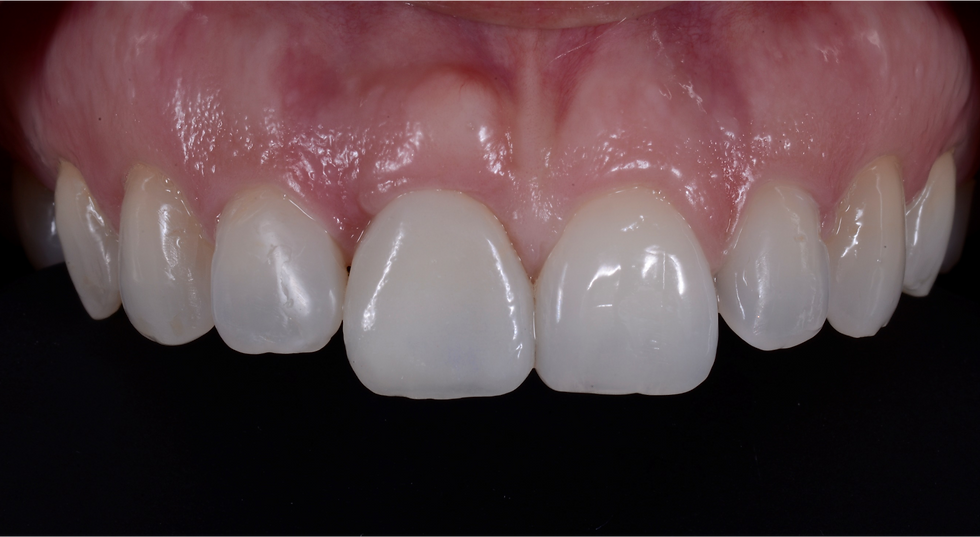

Final zirconia screw-retained crown

Final smile